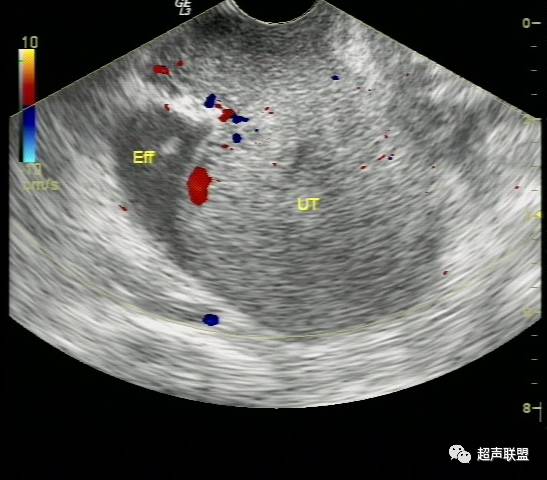

宫外孕破裂出血的声像图 宫外孕发生率占妊娠的0.5%~1%,其中95%为输卵管妊娠。常与输卵管炎、输卵管手术后输卵管不同程度粘连、受精卵移行不畅有关。输卵管妊娠时由于缺乏完整蜕膜,孕卵植入后,其绒毛借蛋白分解酶的作用直接侵蚀管壁肌层,因输卵管管壁薄弱,不能适应受精卵的发育,当受精卵发育到一定程度后,常引起流产或破裂。由于输卵管肌层血管丰富,短期内即可大量出血使患者陷入休克。由于破裂口周围形成凝血块或未凝血液,从而超声表现为形态不规整、边界不清楚、回声紊乱的混合性包块,并有盆腔积液,积液中含血细胞形成的密集点状回声。

(4)卵巢囊肿破裂,患者过去多有囊肿病史,突发剧烈腹痛亦多有重击、及妇科检查等诱因。巧克力囊肿则多有痛经病史,由于其囊壁较厚一般不容易破裂,但当月经期出血量多时仍可以破裂。超声检查发现其子宫大小亦多正常,子宫内膜不厚,患者亦无停经史,尿HCG检查阴性。  总之,宫外孕破裂出血是妇产科最常见的急腹症之一。出血量大者,病情特别危急,需要立即做出诊断和鉴别诊断,以便采取适当而有效的治疗措施。对于一个临床主要表现为下腹剧烈疼痛,超声表现为附件或盆腔混合性包块,伴有盆腔甚至腹腔积液的妇科急症患者,检查者应该想到上述疾病。超声声像图注意观察子宫大小、子宫内膜厚度、盆腔积液的内部回声等。并尽可能详细询问月经史、性生活史及临床病史,结合尿或血HCG检查、血常规检查等,进行综合分析判断。随着超声仪技术的发展,阴道彩色多普勒检查的应用,宫外孕包块内滋养层血流的检测,将更有助于宫外孕破裂的诊断及鉴别诊断。

宫外孕破裂出血是妇产科最常见的急腹症之一。出血量大者,病情特别危急,需要立即作出诊断和鉴别诊断,以便采取适当而有效的治疗措施。对于一个临床主要表现为下腹剧痛,超声表现为:子宫轻度增大,子宫内膜不同程度增厚,宫内未见妊娠囊;一侧附件区可探及不均质包块,包块形态欠规则,边界不清楚,回声紊乱;陶氏窝可见多少不一不规则的液性暗区,暗区中有密集点状回声。盆腔甚至腹腔积液的妇产科急症患者。检查者应该想到上述疾病。并尽可能详细询问月经史、性生活史及临床病史,结合尿或血HCG检查、血常规检查等,进行综合分析判断。随着超声仪技术的发展,阴道彩色多普勒检查的应用,宫外孕包块内滋养层血流的检测,将更有助于宫外孕破裂的诊断及鉴别诊断。